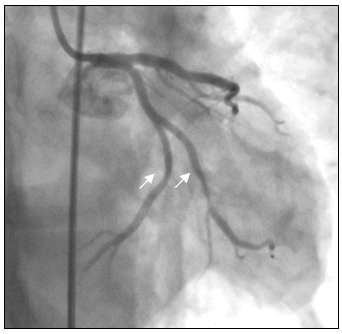

Tại phòng thông tim huyết áp bệnh nhân thấp 80/60mmHg nên chúng tôi không dùng Nitroglycerin. Sau khi chụp thấy hẹp nặng lan tỏa ở cả ba nhánh của động mạch vành, không loại trừ do co thắt nên chúng tôi đã tiến hành bơm 500µg Nitroglycerin vào động mạch vành. Kết quả chụp lại hiện tượng trên hoàn toàn biến mất, động mạch vành phải và trái thâm nhiễm nhẹ nhưng đều có kích thước lớn hơn nhiều so với ban đầu, dòng chảy TIMI 3 (hình 3a-3b), đồng thời huyết áp của bệnh nhân cũng cải thiện rõ 120/80 mmHg.

Hình 3a: Nhánh LCX, OM và LAD sau khi bơm Nitroglycerin